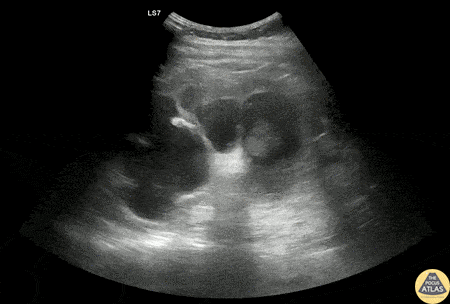

Renal/GU - Severe Hydronephrosis

30s M PMH HIV, latent TB p/w acute onset flank pain with dysuria. He was found to be febrile and tachycardic. Initial workup was consistent with sepsis due to pyelonephritis. Renal POCUS is shown here, demonstrating severe hydronephrosis, with distortion of the calyceal collecting system as well as thinning of the renal cortex. CT imaging of the abdomen/pelvis demonstrated ureteropelvic junction stenosis causing significant hydronephrosis. Urology was consulted and the patient was admitted for treatment of pyelonephritis as well as further workup of the renal abnormalities. Dr. Nimish Bhatt, US Fellow Denver Health Emergency Ultrasound Fellowship